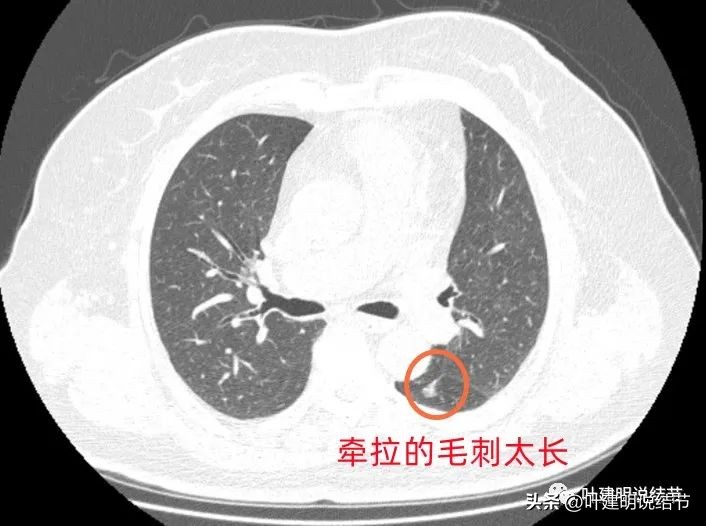

病灶6:左下叶背段磨玻璃结节,伴有一长毛刺,牵拉斜裂,感觉这样的病灶如果是肿瘤,收缩力太强了,不符合的,而且毛刺过长,纤细,又只有这么一根毛刺。更符合慢性炎伴纤维增生之类。